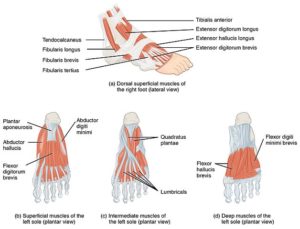

En el pie hay un total de 29 músculos responsables del movimiento de los huesos y articulaciones. Estos se encuentran unidos a través de tendones desde el tobillo y el talón hasta los dedos.

10 de estos músculos se originan en la pierna y refuerzan la articulación del tobillo llegando hasta el pie, por ese motivo se denominan músculos extrínsecos.

Los músculos extrínsecos del pie se ocupan de mantener la posición del tobillo y del talón para el equilibrio.

Los 19 músculos restantes son denominados músculos intrínsecos. Tienen su origen dentro de los límites del pie, es decir desde el tobillo hasta los dedos.

Estos músculos contribuyen en las funciones de apoyo y trabajan ayudando a los músculos extrínsecos y las aponeurosis plantar y dorsal, en el soporte y la distribución del peso corporal así como en el control de la marcha.

Los músculos intrínsecos se dividen a su vez en músculos de la planta y músculos del dorso del pie. Los músculos del dorso del pie son dos extensores; el extensor corto de los dedos y el extensor corto del primer dedo.

El sistema muscular de la planta del pie es mucho más complicado y se subdivide en cuatro estratos, de superficial a profundo, según el plano en el que se ubique el grupo muscular.